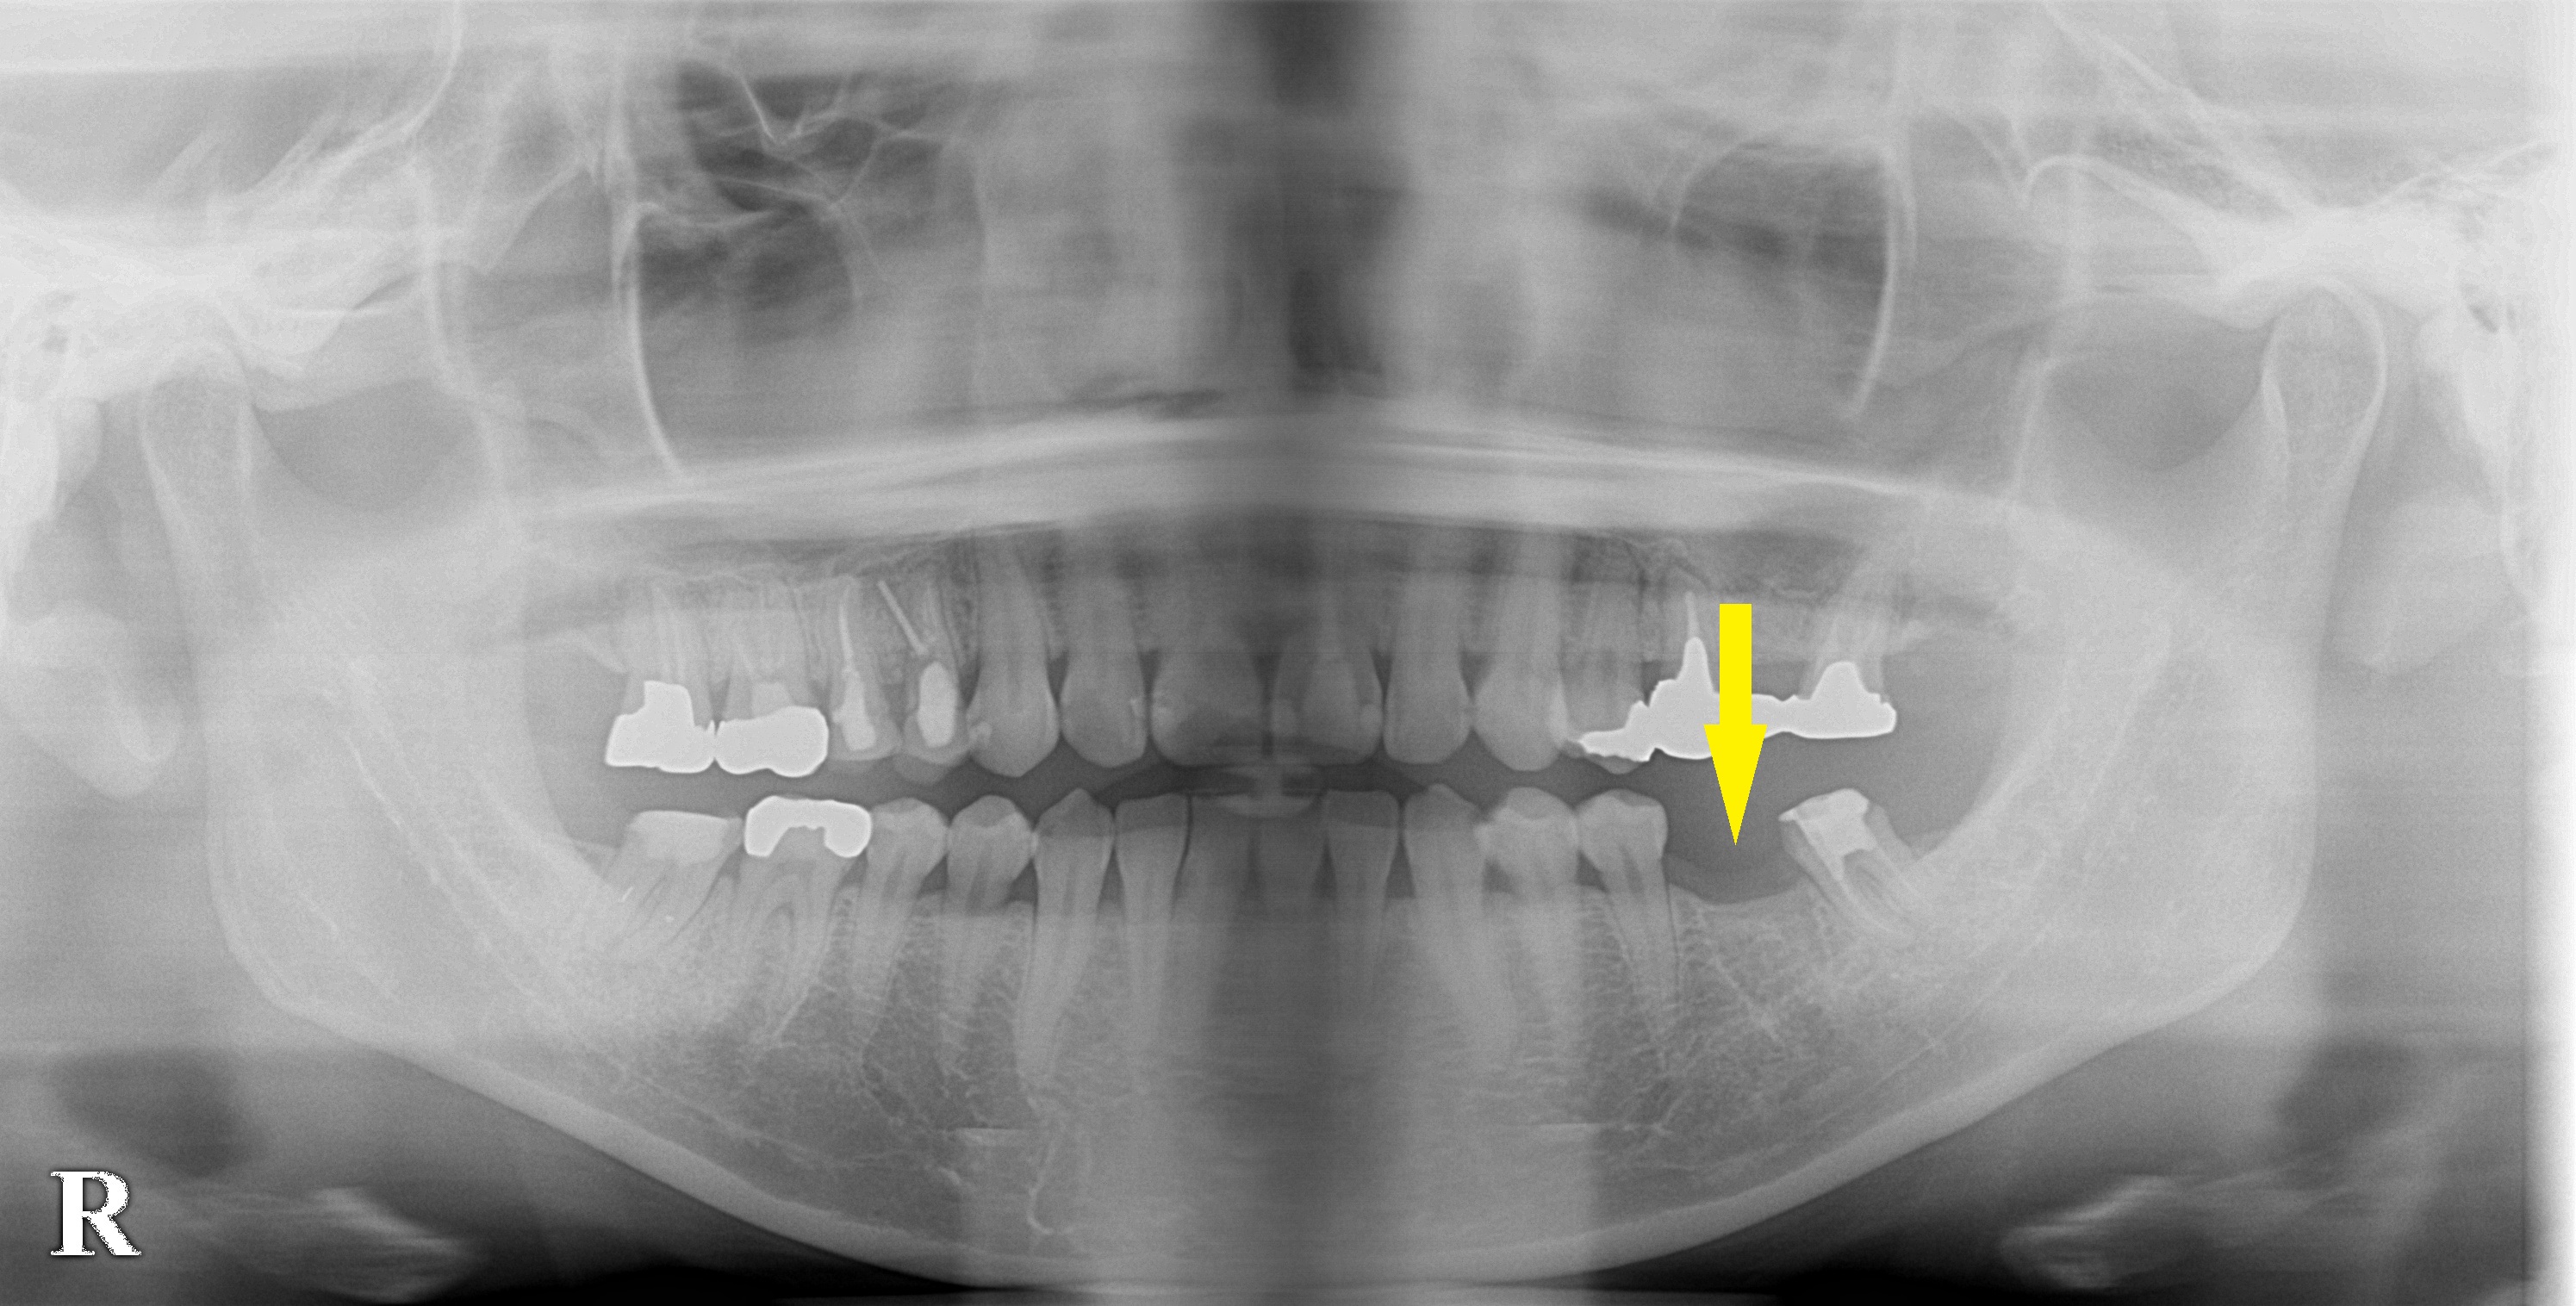

第一大臼歯1本の欠損を、ブリッジでなくてインプラントで 今週のインプラント症例 2019.12.122026.01.20 患者様は名古屋在住の30代女性。 左下顎第一大臼歯を抜歯されて、ブリッジで治療すると説明されたそうです。 手前の歯は、全くきれいな歯でしたので、これを削ってブリッジにすることはためらわれたため、インプラント治療を希望して当院に相談に来られました。 レントゲン写真やCTで、骨の量は十分でしたので、ご希望どおりインプラントをお勧めしました。 本日、同部に1本のインプラント埋入術を行なっております。 症例・コラム一覧に戻る